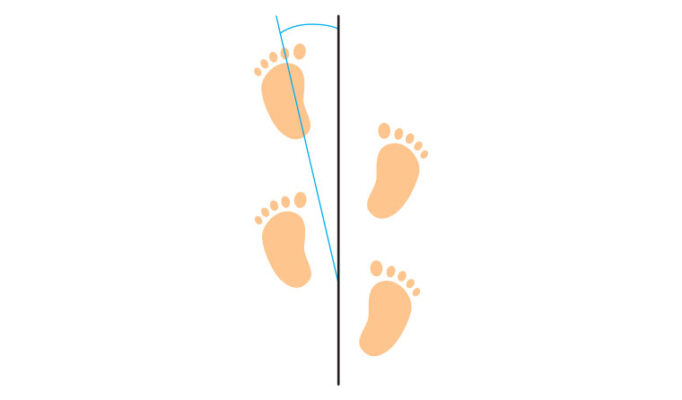

Lượng giá dáng đi và đo góc tiến bàn chân (FPA)

Phân tích dáng đi, xem xét sự canh chỉnh ở mặt phẳng đứng dọc (nhìn từ phía bên, đánh giá gập/duỗi), mặt phẳng trán (nhìn trước sau, đánh giá dạng/khép) và mặt phẳng cắt ngang (góc tiến bàn chân, đánh giá sự xoay).

Góc tiến bàn chân được định nghĩa là góc giữa trục của bàn chân và đường tiến ra trước. Theo quy ước, góc tiến vào trong là âm, và ra ngoài là dương. Đánh giá trên lâm sàng thường là hướng dẫn bệnh nhân đi hướng về người khám. Góc tiến bàn chân thường dương tính nhẹ (6-10°) suốt quá trình tăng trưởng, với góc ra ngoài nhẹ ở trẻ nhỏ (do tăng xoay ngoài khớp háng) và người già (do giảm dần xoay trong khớp háng). Cần đo và ghi lại đê theo dõi tiến triển.

Cần lưu ý là góc tiến bàn chân có thể bình thường ngay cả ở những trường hợp có biến dạng nặng (như kết hợp vặn trước xương đùi và vặn xoay ngoài xương chày. Bù trừ xoay có thể xảy ra ở >50% trường hợp bệnh nhân, do đó cần khám đầy đủ ngay cả khi bệnh nhân đi với dáng đi có vẻ bình thường và có góc tiến bàn chân bình thường. Với những trường hợp bệnh nhân bị bệnh lý thần kinh có thể cần lượng giá dáng đi nâng cao (ở phòng nghiên cứu).